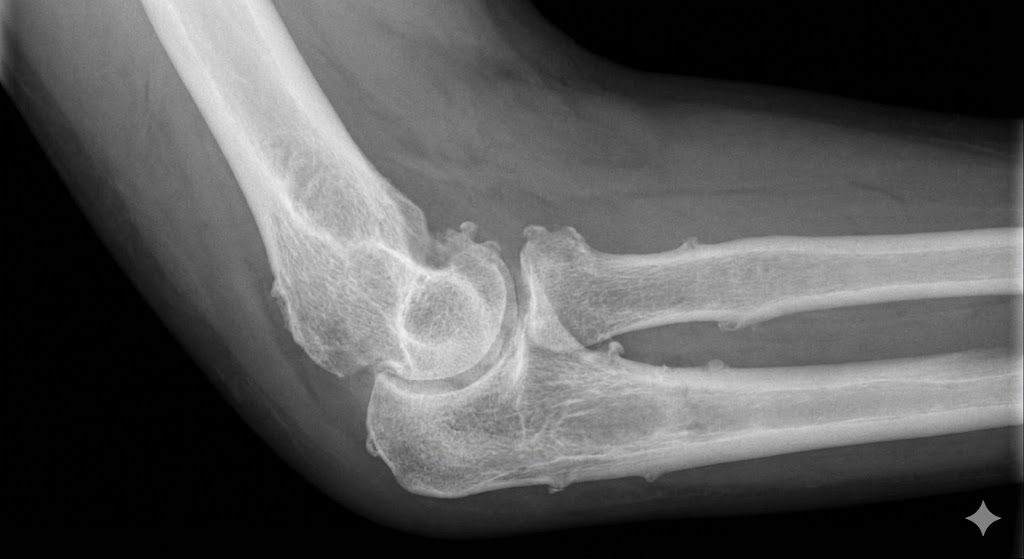

「病院で『骨が変形してトゲ(骨棘)ができている』と言われた」

日本の一般住民を対象とした大規模調査で、50歳以上の約4人に1人(25.2%)に「肘の変形(変形性肘関節症)」が見つかりました。

しかし、そのうち「痛み」を感じていたのは、わずか「0.9%」でした。

つまり、「変形がある人の96%は、痛くない(無症状)」なのです。

これは、どういうことでしょうか? 「骨が変形している(構造)」から、「必ず痛い(症状)」わけではない、ということです。 あなたの「変形」や「骨棘」は、長年の使用に耐えて関節を安定させるための「適応」であり、それ自体が痛みの犯人とは限らないのです。